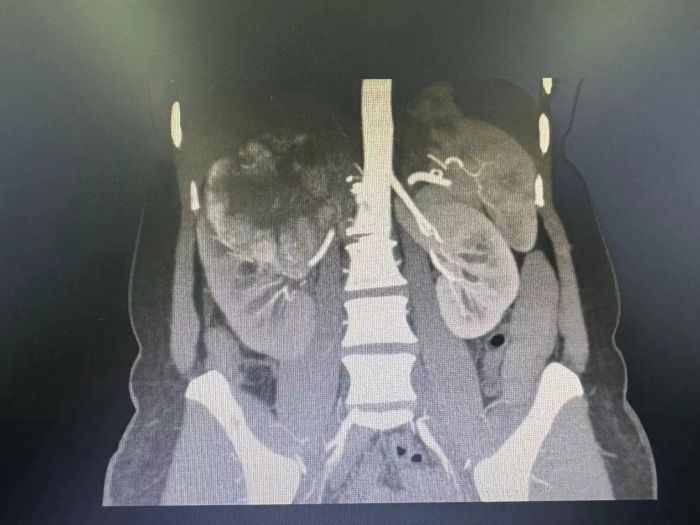

靶向联合免疫治疗后

完善相关靶向治疗及免疫治疗前检查后,排除用药禁忌症,申智勇博士团队予陈女士进行了规律、规范的肾透明细胞肾细胞癌靶免联合术前新辅助治疗,并做好肿瘤全程管理及追踪。用药治疗期间陈女士未感任何不适,没有严重不良反应。用药一周后再次复查下腹部CT平扫及下腹部CT增强,发现右肾肿瘤呈中心液化坏死,与肝脏界限明显清晰,肾门淋巴结较治疗前明显缩小。“可以手术”!在石家齐教授、申智勇博士的指导下,泌尿外科积极完善术前相关准备,同时请影像科、肝胆外科、胃肠外科、手术麻醉科、ICU、病理科、医务部多学科共同进行四级手术术前讨论,为了确保手术成功,团队制定了缜密的手术方案,在石家齐教授和申智勇博士的带领下,手术团队历经3个多小时,顺利完成了“经腹腹腔镜下右肾癌根治术+肾门淋巴结清扫术”。术后陈女士生命体征平稳,经精准治疗及精细术后护理,陈女士术后2天下床活动,恢复良好,右侧腰背部疼痛症状明显消失,现已经出院恢复正常生活。